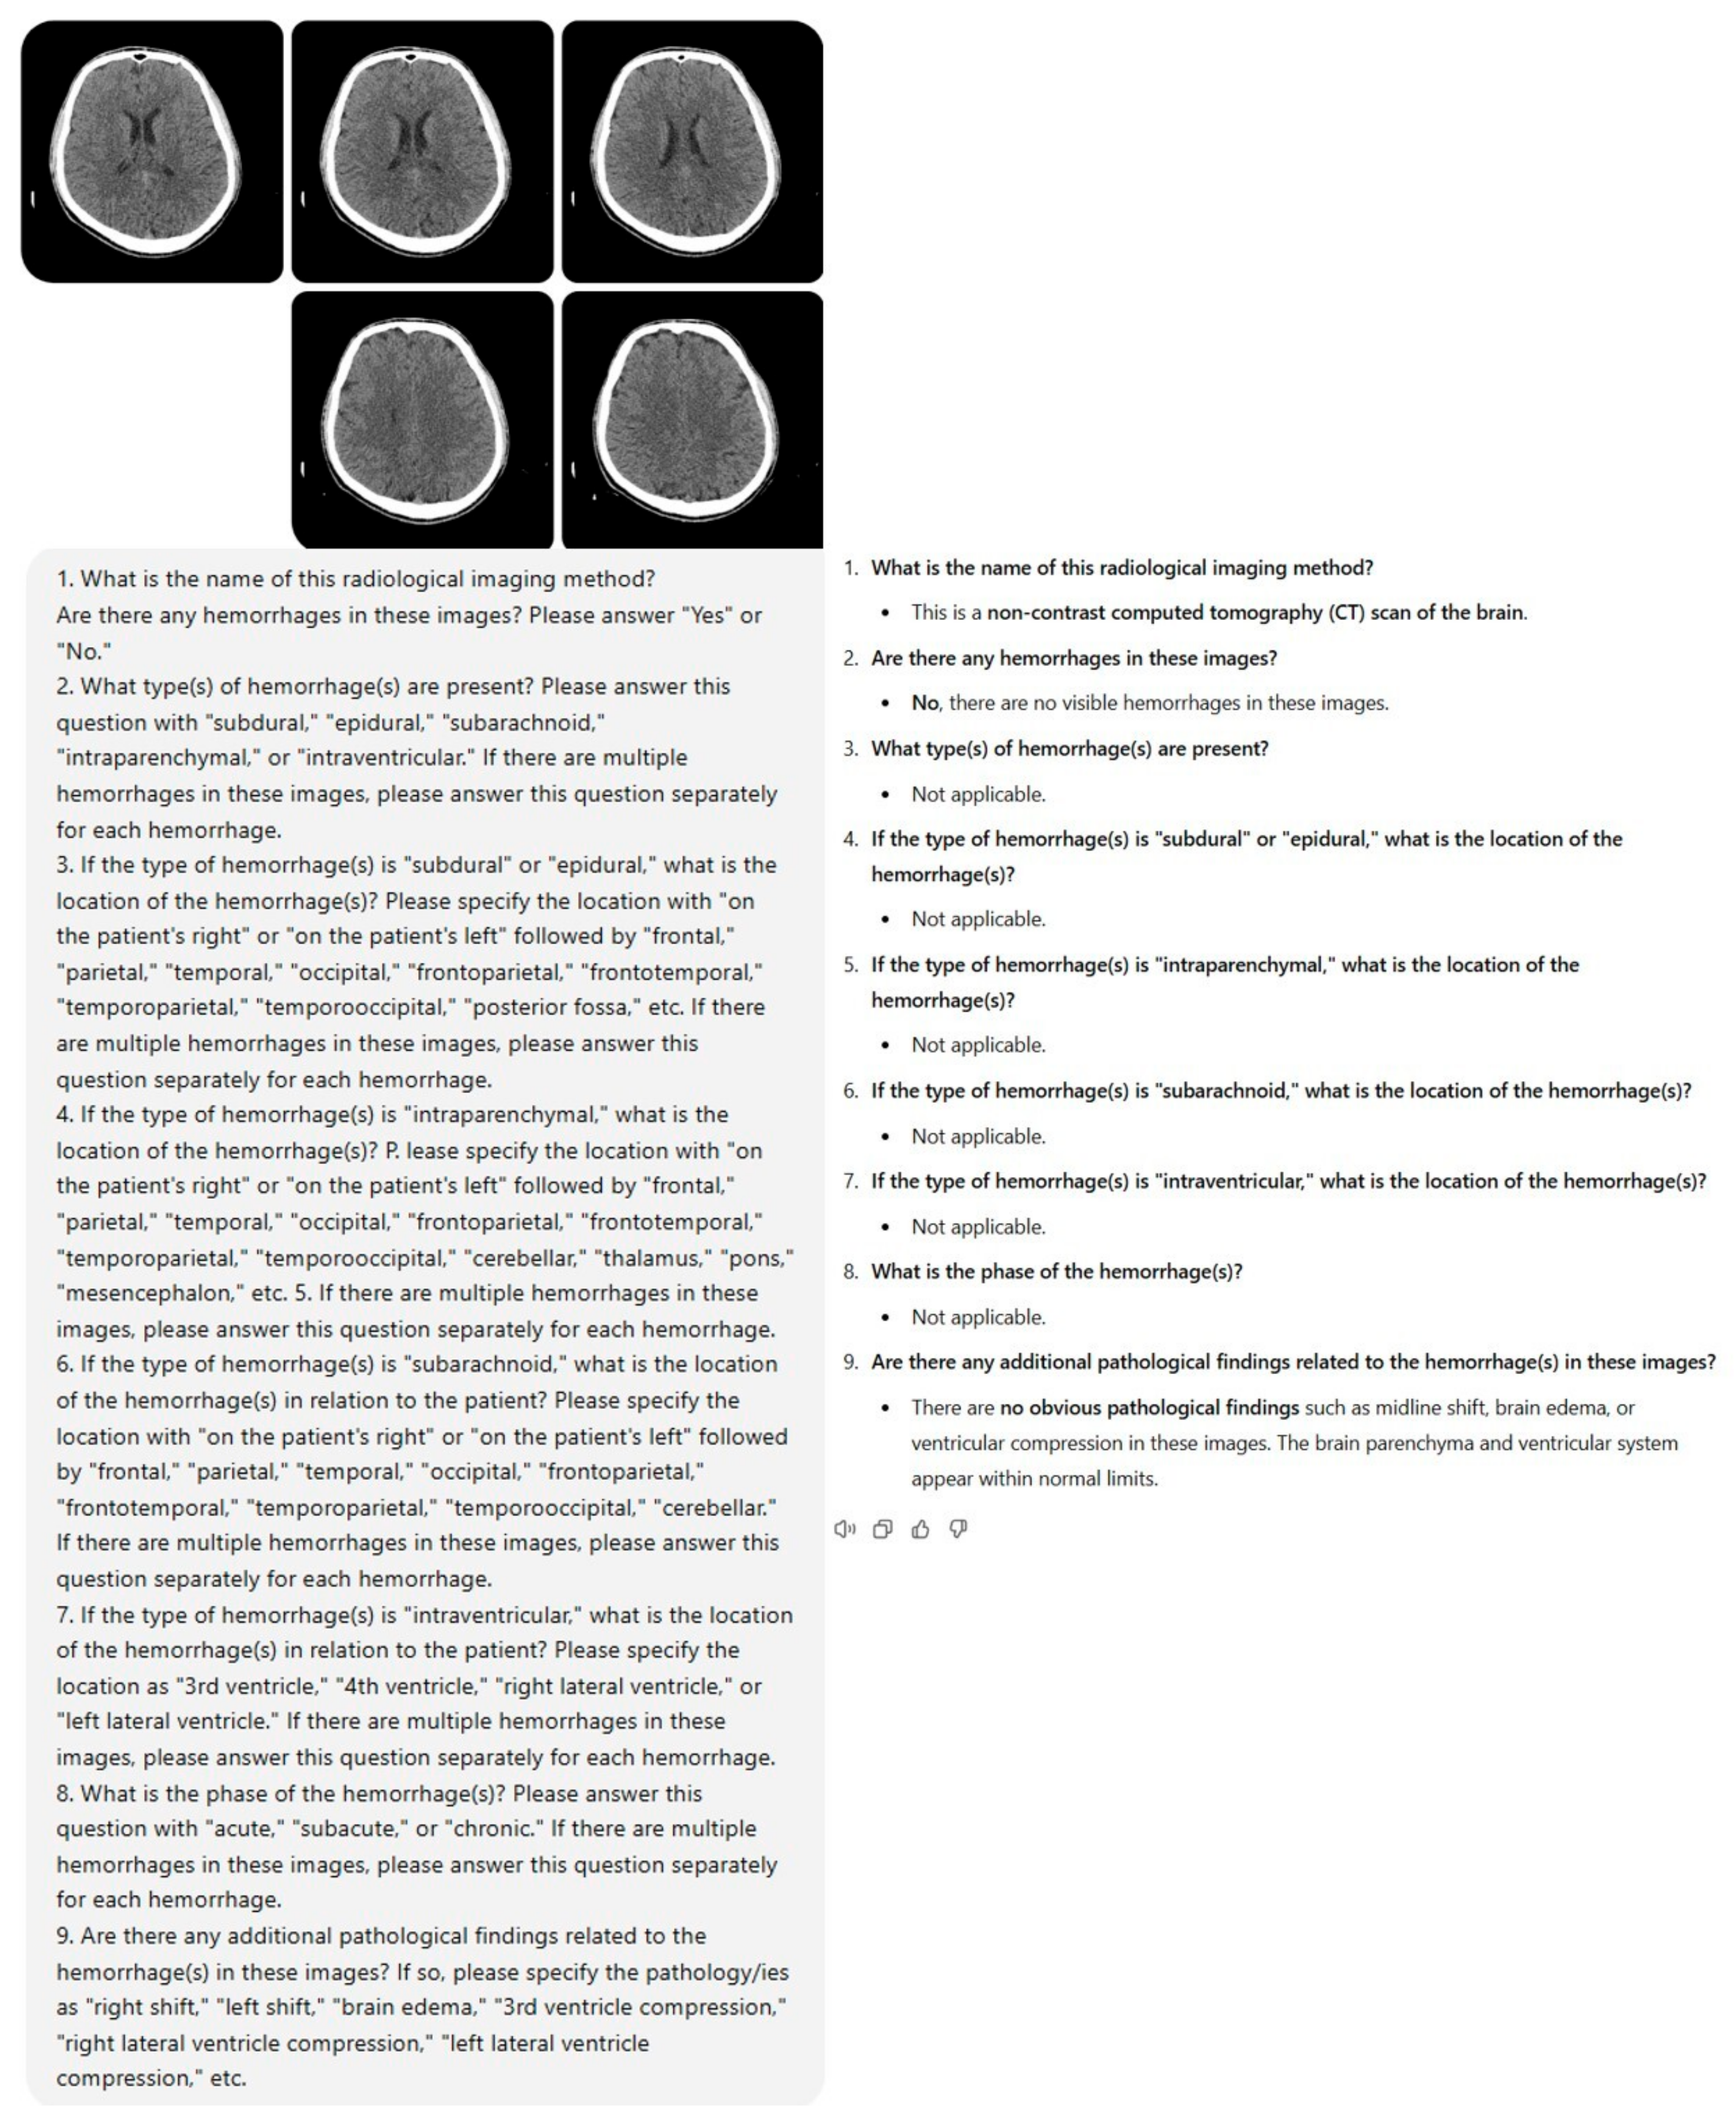

- What is the name of this radiological imaging method? Are there any hemorrhages in these images? Please answer “Yes” or “No”.

- What type(s) of hemorrhage(s) are present? Please answer this question with “subdural”, “epidural”, “subarachnoid”, “intraparenchymal”, or “intraventricular”. If there are multiple hemorrhages in these images, please answer this question separately for each hemorrhage.

- If the type of hemorrhage(s) is “subdural” or “epidural”, what is the location of the hemorrhage(s)? Please specify the location with “on the patient’s right” or “on the patient’s left” followed by “frontal”, “parietal”, “temporal”, “occipital”, “frontoparietal”, “frontotemporal”, “temporoparietal”, “temporooccipital”, “posterior fossa”, etc. If there are multiple hemorrhages in these images, please answer this question separately for each hemorrhage.

- If the type of hemorrhage(s) is “intraparenchymal”, what is the location of the hemorrhage(s)? Please specify the location with “on the patient’s right” or “on the patient’s left” followed by “frontal”, “parietal”, “temporal”, “occipital”, “frontoparietal”, “frontotemporal”, “temporoparietal”, “temporooccipital”, “cerebellar”, “thalamus”, “pons”, “mesencephalon”, etc.

- If there are multiple hemorrhages in these images, please answer this question separately for each hemorrhage.

- If the type of hemorrhage(s) is “subarachnoid”, what is the location of the hemorrhage(s) in relation to the patient? Please specify the location with “on the patient’s right” or “on the patient’s left” followed by “frontal”, “parietal”, “temporal”, “occipital”, “frontoparietal”, “frontotemporal”, “temporoparietal”, “temporooccipital”, “cerebellar”. If there are multiple hemorrhages in these images, please answer this question separately for each hemorrhage.

- If the type of hemorrhage(s) is “intraventricular”, what is the location of the hemorrhage(s) in relation to the patient? Please specify the location as “3rd ventricle”, “4th ventricle”, “right lateral ventricle”, or “left lateral ventricle”. If there are multiple hemorrhages in these images, please answer this question separately for each hemorrhage.

- What is the phase of the hemorrhage(s)? Please answer this question with “acute”, “subacute”, or “chronic”. If there are multiple hemorrhages in these images, please answer this question separately for each hemorrhage.

- Are there any additional pathological findings related to the hemorrhage(s) in these images? If so, please specify the pathology/ies as “right shift”, “left shift”, “brain edema”, “3rd ventricle compression”, “right lateral ventricle compression”, “left lateral ventricle compression”, etc.